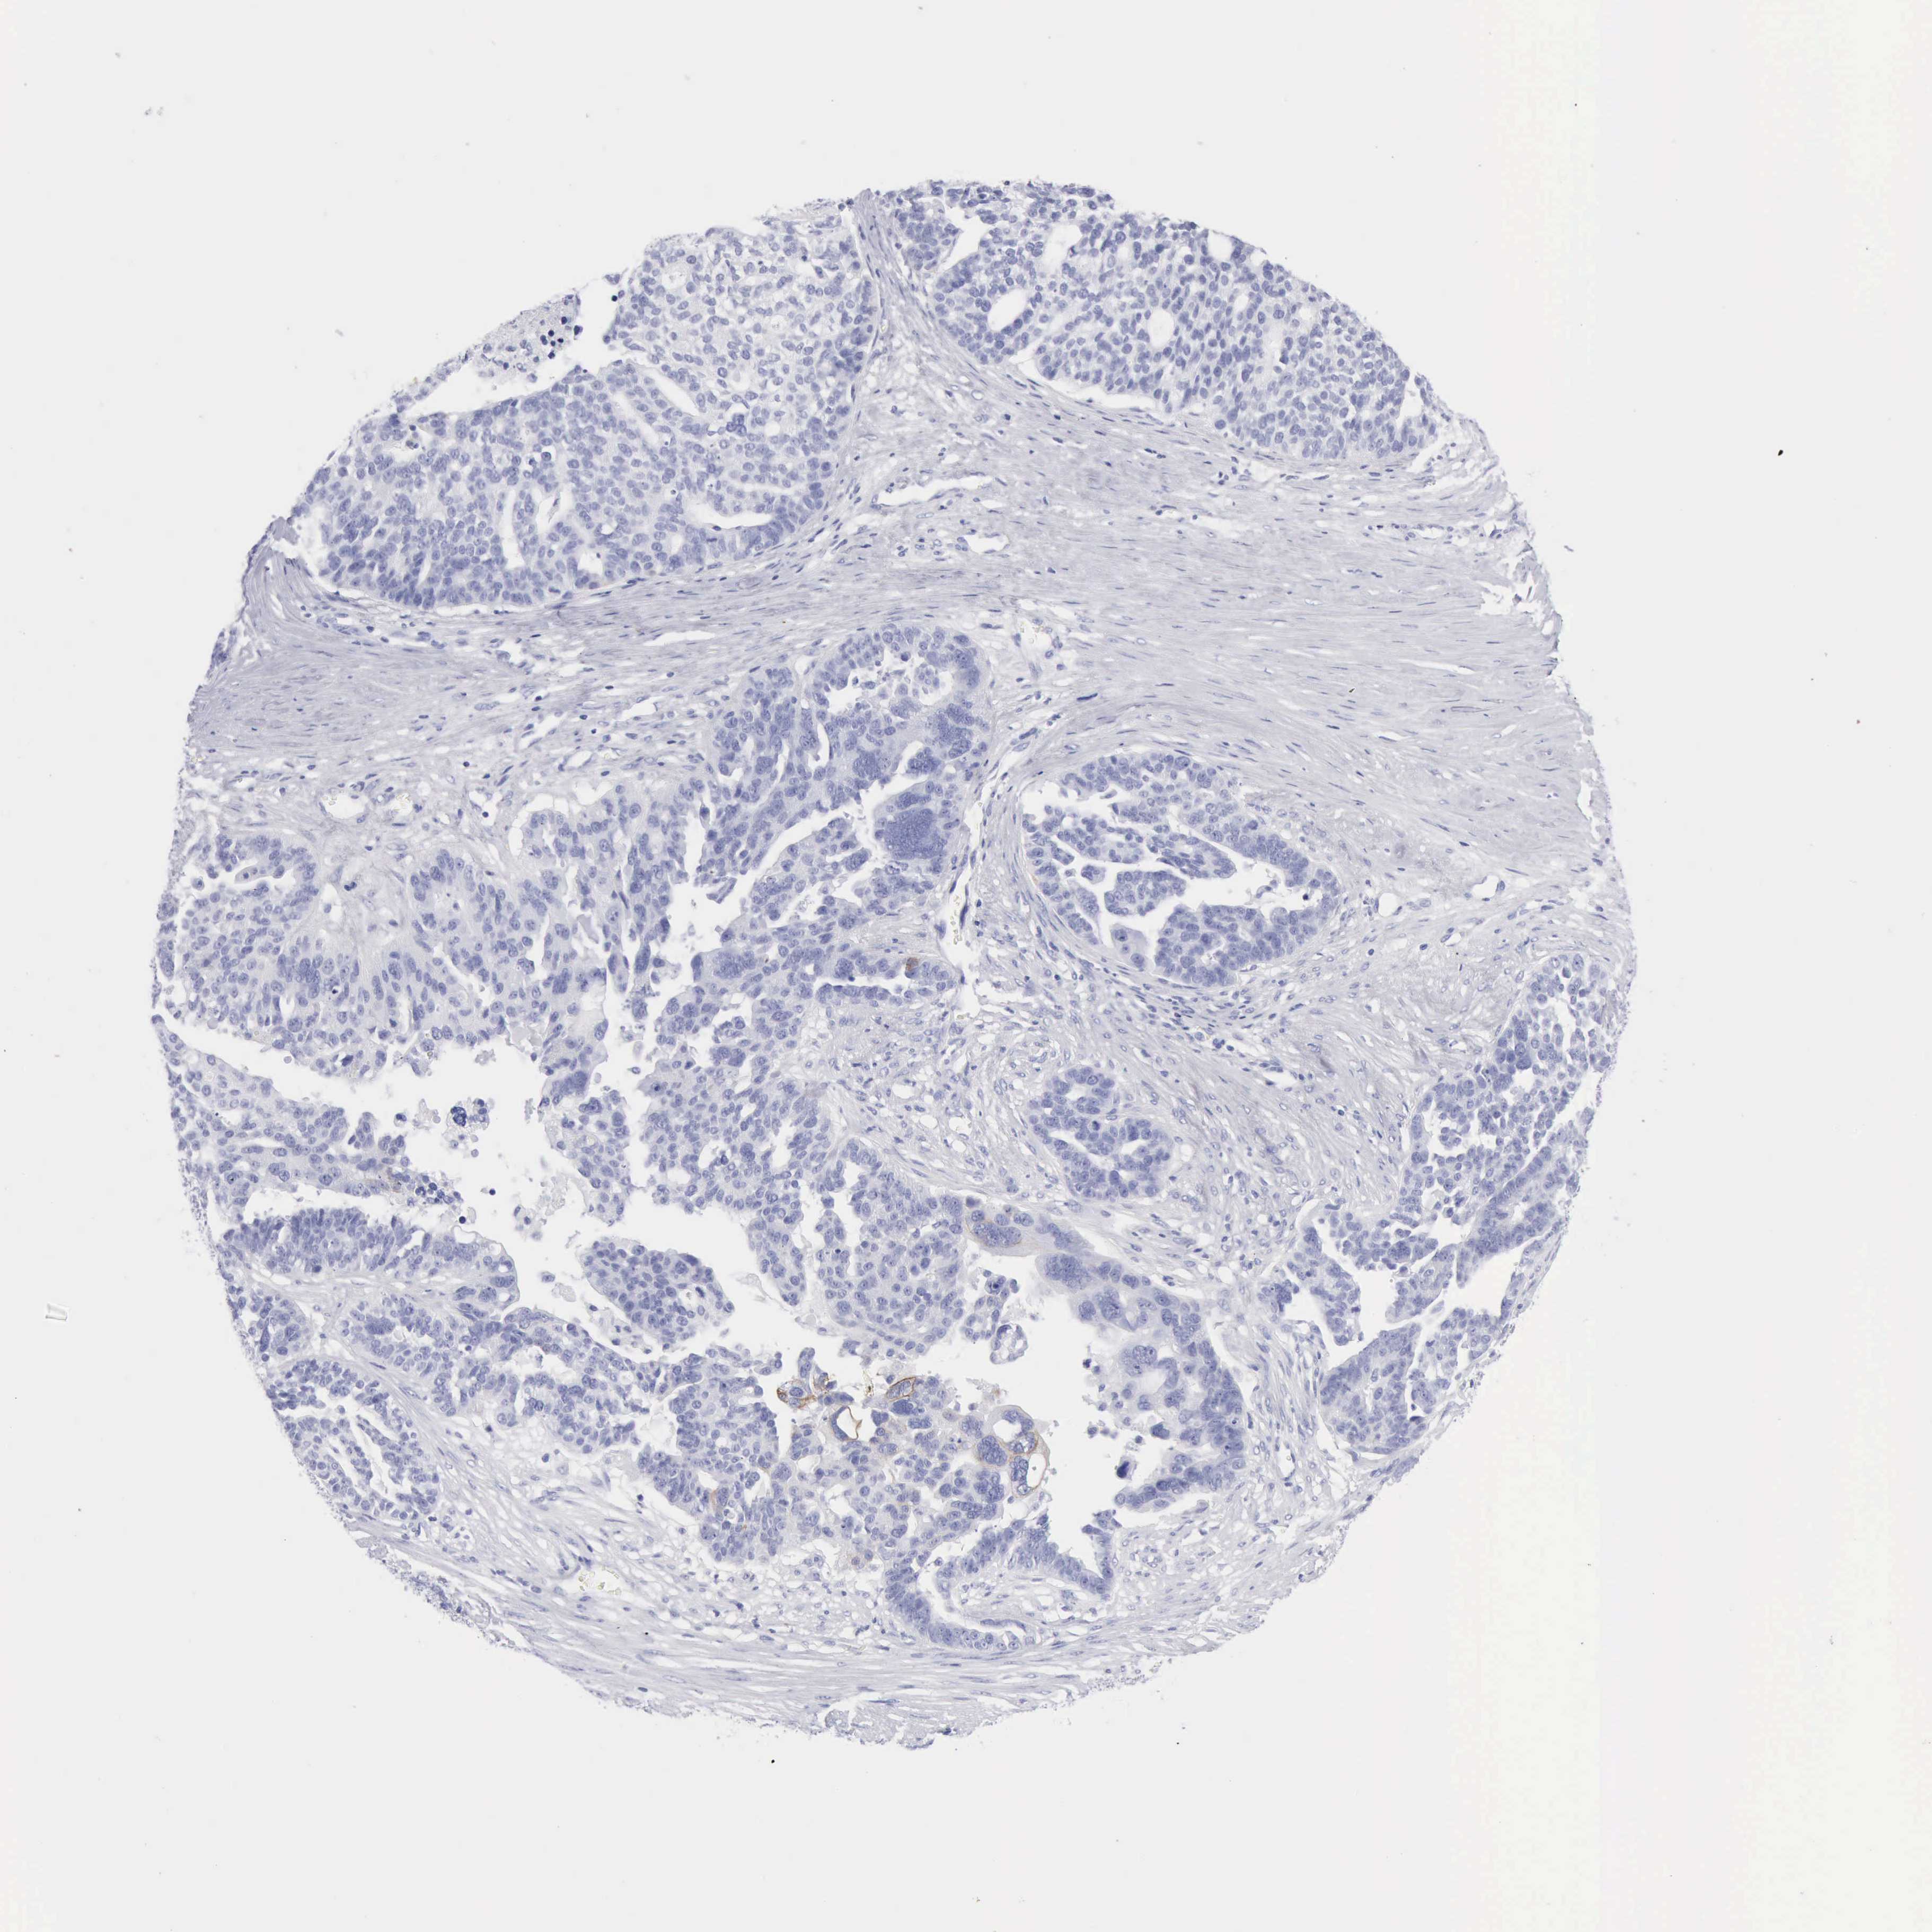

OVARIAN CANCER - Protein expressioni

A mouse-over function shows sample information and annotation data. Click on an image to view it in a full screen mode. Samples can be filtered based on level of antibody staining by selecting one or several of the following categories: high, medium, low and not detected. The assay and annotation is described here.

Note that samples used for immunohistochemistry by the Human Protein Atlas do not correspond to samples in the TCGA dataset.

Antibody stainingi

Antibody staining in the annotated cell types in the current human tissue is reported as not detected, low, medium, or high, based on conventional immunohistochemistry profiling in selected tissues. This score is based on the combination of the staining intensity and fraction of stained cells.

Each image is clickable and will lead to virtual microscopy that enables deeper exploration of all samples and also displays staining intensity scores, fraction scores and subcellular localization as well as patient and tissue information for each sample.

Antibody HPA059479

Antibody CAB000027

Cystadenocarcinoma, serous, NOS

Cystadenocarcinoma, mucinous, NOS

Carcinoma, endometroid